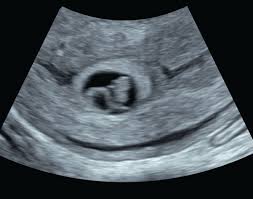

When we went back for our second ultrasound at 9 weeks and 3 days our baby is measuring at 8 weeks and 6 days.

Four days later Friday I came in and they are now measuring my baby as 7 to 10 days behind because he had very slow growth between the two ultrasounds. If you measure 30cm 12in or less at 32 weeks or your customised results are below your range your midwife may offer you an ultrasound scan to be on the safe side. 3 days later at 9 weeks exactly I scheduled an appointment with my RE to confirm the baby was still doing well. But we had a positive pregnancy test about 55 weeks before this exam which would supposedly be the first day of my last period if we were off on our dates. Baby was measuring in the 20th percentile at 32 weeks midwife said this was no issue because everything looked fine and I am pretty small myself. They asked me to return for another scan. I had a private early scan at 7 weeks and there was only the gestational sac measuring 2177mm and a yolk sac. They did an internal ultrasound and the tech said the fetus is too. Born at 38wks at 6lbs so not that small and healthy.

Most women dont find out that theyve had a late miscarriage until 12 weeks when they have. 9 weeks pregnant and measuring small slow growth of baby. Today I had my 3rd us. I was scared and anxious that my baby may stop growing any moment. For now I just want you to know that measuring small could just be that you ovulated later in your cycle than was presumed. 3 days later at 9 weeks exactly I scheduled an appointment with my RE to confirm the baby was still doing well. This type of scan is called a growth scan.